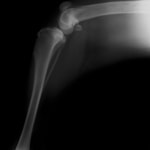

■ミニチュアダックスフント 1歳 去勢オス

前肢の成長板早期閉鎖、前肢の重度の外反変形が認められました。

関節面の変形が重度に認められます。